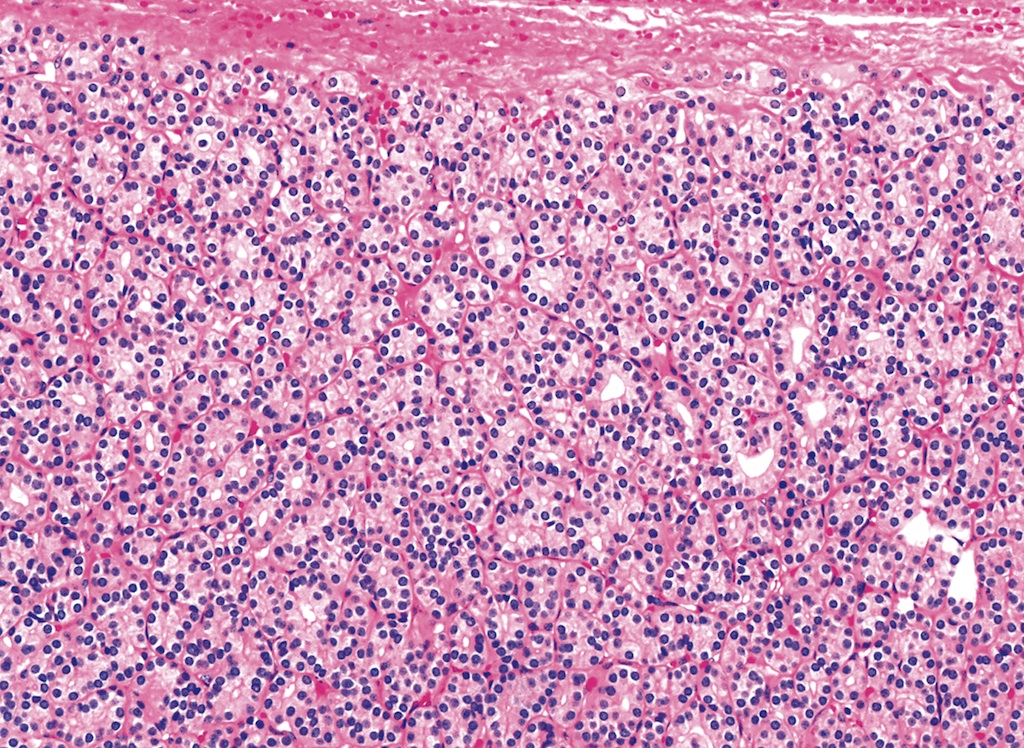

Microscopic (histologic) description

- Architecturally and cytologically different from surrounding gland

- Compression signs in surrounding thyroid tissue

- Encapsulated; thin or moderately thick capsule

- Architectural patterns (can be seen in any combination)

- Normofollicular (simple): size similar to normal thyroid follicles

- Microfollicular (fetal): smaller follicles, small amount of intraluminal colloid

- Macrofollicular (colloid): large follicles, flattened epithelium, abundant colloid

- Solid / trabecular (embryonal): minimal or no colloid

- Focal papillary pattern, occasionally; especially in hyperfunctioning adenoma and follicular adenoma with papillary hyperplasia

- Cuboidal to low columnar cells

- Small round nuclei, smooth nuclear boundary, uniformly hyperchromatic or euchromatic, dense chromatin, absent nuclear features of papillary thyroid carcinoma, nuclear score 0 or 1 (JAMA Oncol 2016;2:1023)

- Inconspicuous nucleoli

- Rarely, lipid filled vacuoles in cytoplasm

- Mitoses are uncommon

- Scant stroma

- Secondary changes: fibrosis, hyalinization, hemorrhage, hemosiderin deposition, edema, cystic degeneration, calcification, osseous or cartilaginous metaplasia

Microscopic (histologic) images

Contributed by Shipra Agarwal, M.D., Andrey Bychkov, M.D., Ph.D., Mark R. Wick, M.D., Asmaa Gaber Abdou, M.D. and AFIP

Patterns: